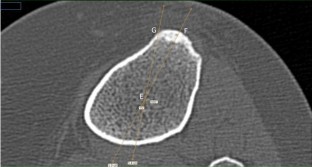

The angle formed from the tibial geometric centre to the intersection of both lines from the middle of the tibial tuberosity and its medial border was measured in 50 patients. The geometric centre was determined on an axial CT slice at 10 mm below the lateral tibial plateau and transposed to a slice at the level of the most prominent part of the tibial tuberosity. Similar measurements were taken in 25 patients after TKA, in order to simulate the intraoperative appearance of the tibia after making its proximal resection.

This study found that in 90 % of the patients, the medial border of the tibial tuberosity is internally rotated 17°–24° in relation to the line connecting the middle of the tuberosity to the tibial geometric centre. Since this anatomical landmark may be more easily identifiable intraoperatively than the commonly used “medial 1/3”, it can provide a better quantitative reference point and help surgeons achieve a more accurate tibial implant rotational position.